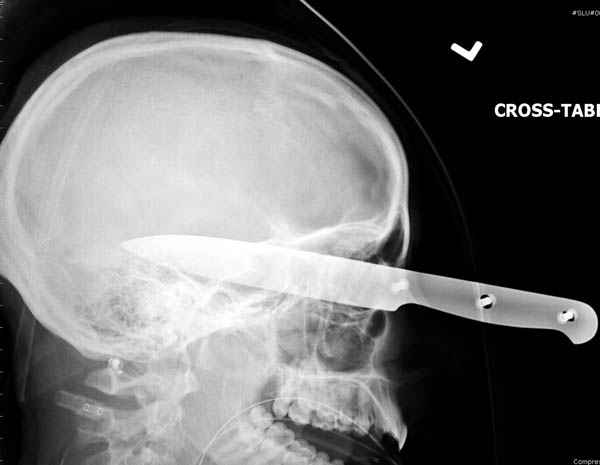

В своих выступлениях я рассказывал, что наши центры в мирное время по пенетрирующим травмам не уступает Ираку или Афганстану, и вот недавно к нам поступила больная 22 лет, травма "ножом в глаз" от бывшей подруги нынешнего "бой френда".

При поступлении в сознании, жаловалась на неприятные ощущения в глазнице.

По протоколу сделаны все необходимые исследования: рентген, ангиограмма с 3Д реконструкцией, где обнаружили что все жизненно важные сосуды не задеты, даже некоторые "сидят" изгибаясь на ноже.

Одним махом нож удалить не удалось, пришлось раскачать и потом двумя руками удалили нож. Рана без кровотечения, обработана и зашита.